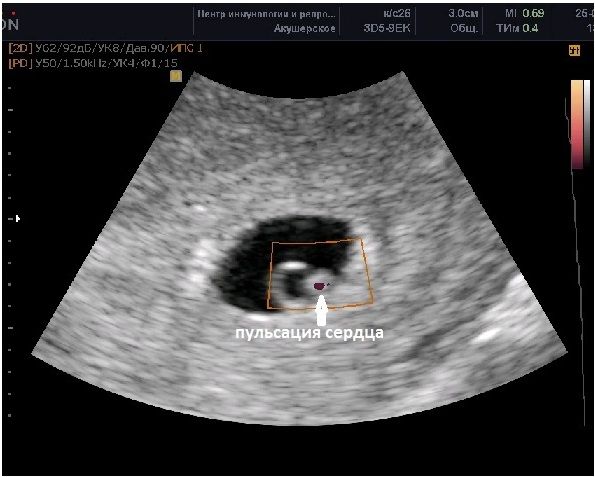

Елена, ну она объяснила, что плодное яйцо внутри чисто чёрное

вот так, например

картинка из интернета:

Бубльгум, а у меня это пространство будто с помехами какими-то

Бубльгум, Оно черное, потому как анэхогенное, а не потому, что там жидкость мутная или не мутная. Жидкость любая по мутности, отражается черным цветом. А вот эмбрион выглядит светлым, ибо плотность выше чем у жидкости. Все органы человека отражают ультразвук по-своему. Цвет зависит от плотности органа: чем он плотнее, тем белее картинка.

Возможно, если бы были какие-то плотные включения в ПЯ, тогда на узи выглядело бы содержимое пегим, с вкраплениями. Но я не знаю таких включений в ПЯ на таком сроке и на таких размерах, там же все микроскопическое у Вас.

Наверное Ваша узистка просто так оценочно высказалась о картинке на мониторе, увидев не чисто черный цвет.